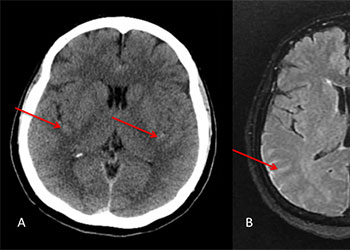

Central Cord Syndrome

Author: Yusef Imani M.D., F.A.A.N.S., Read More!